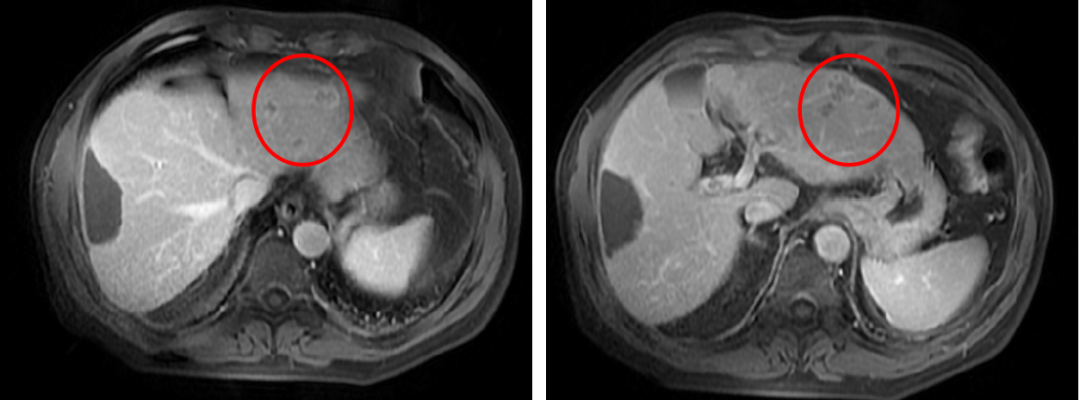

2019年12月3日于门诊复查提示AFP动态快速升高至489.3 ug/L,2019年12月4日MRI示肝内见多发小结节,以肝左叶明显,呈等T1稍长T2信号,DWI呈高信号,增强呈明显强化,考虑复发。于外院再次行TACE术一次。

2020年1月30日复查AFP升高至615 ug/L,MRI复查提示多发小结节增大增多,病情进展。